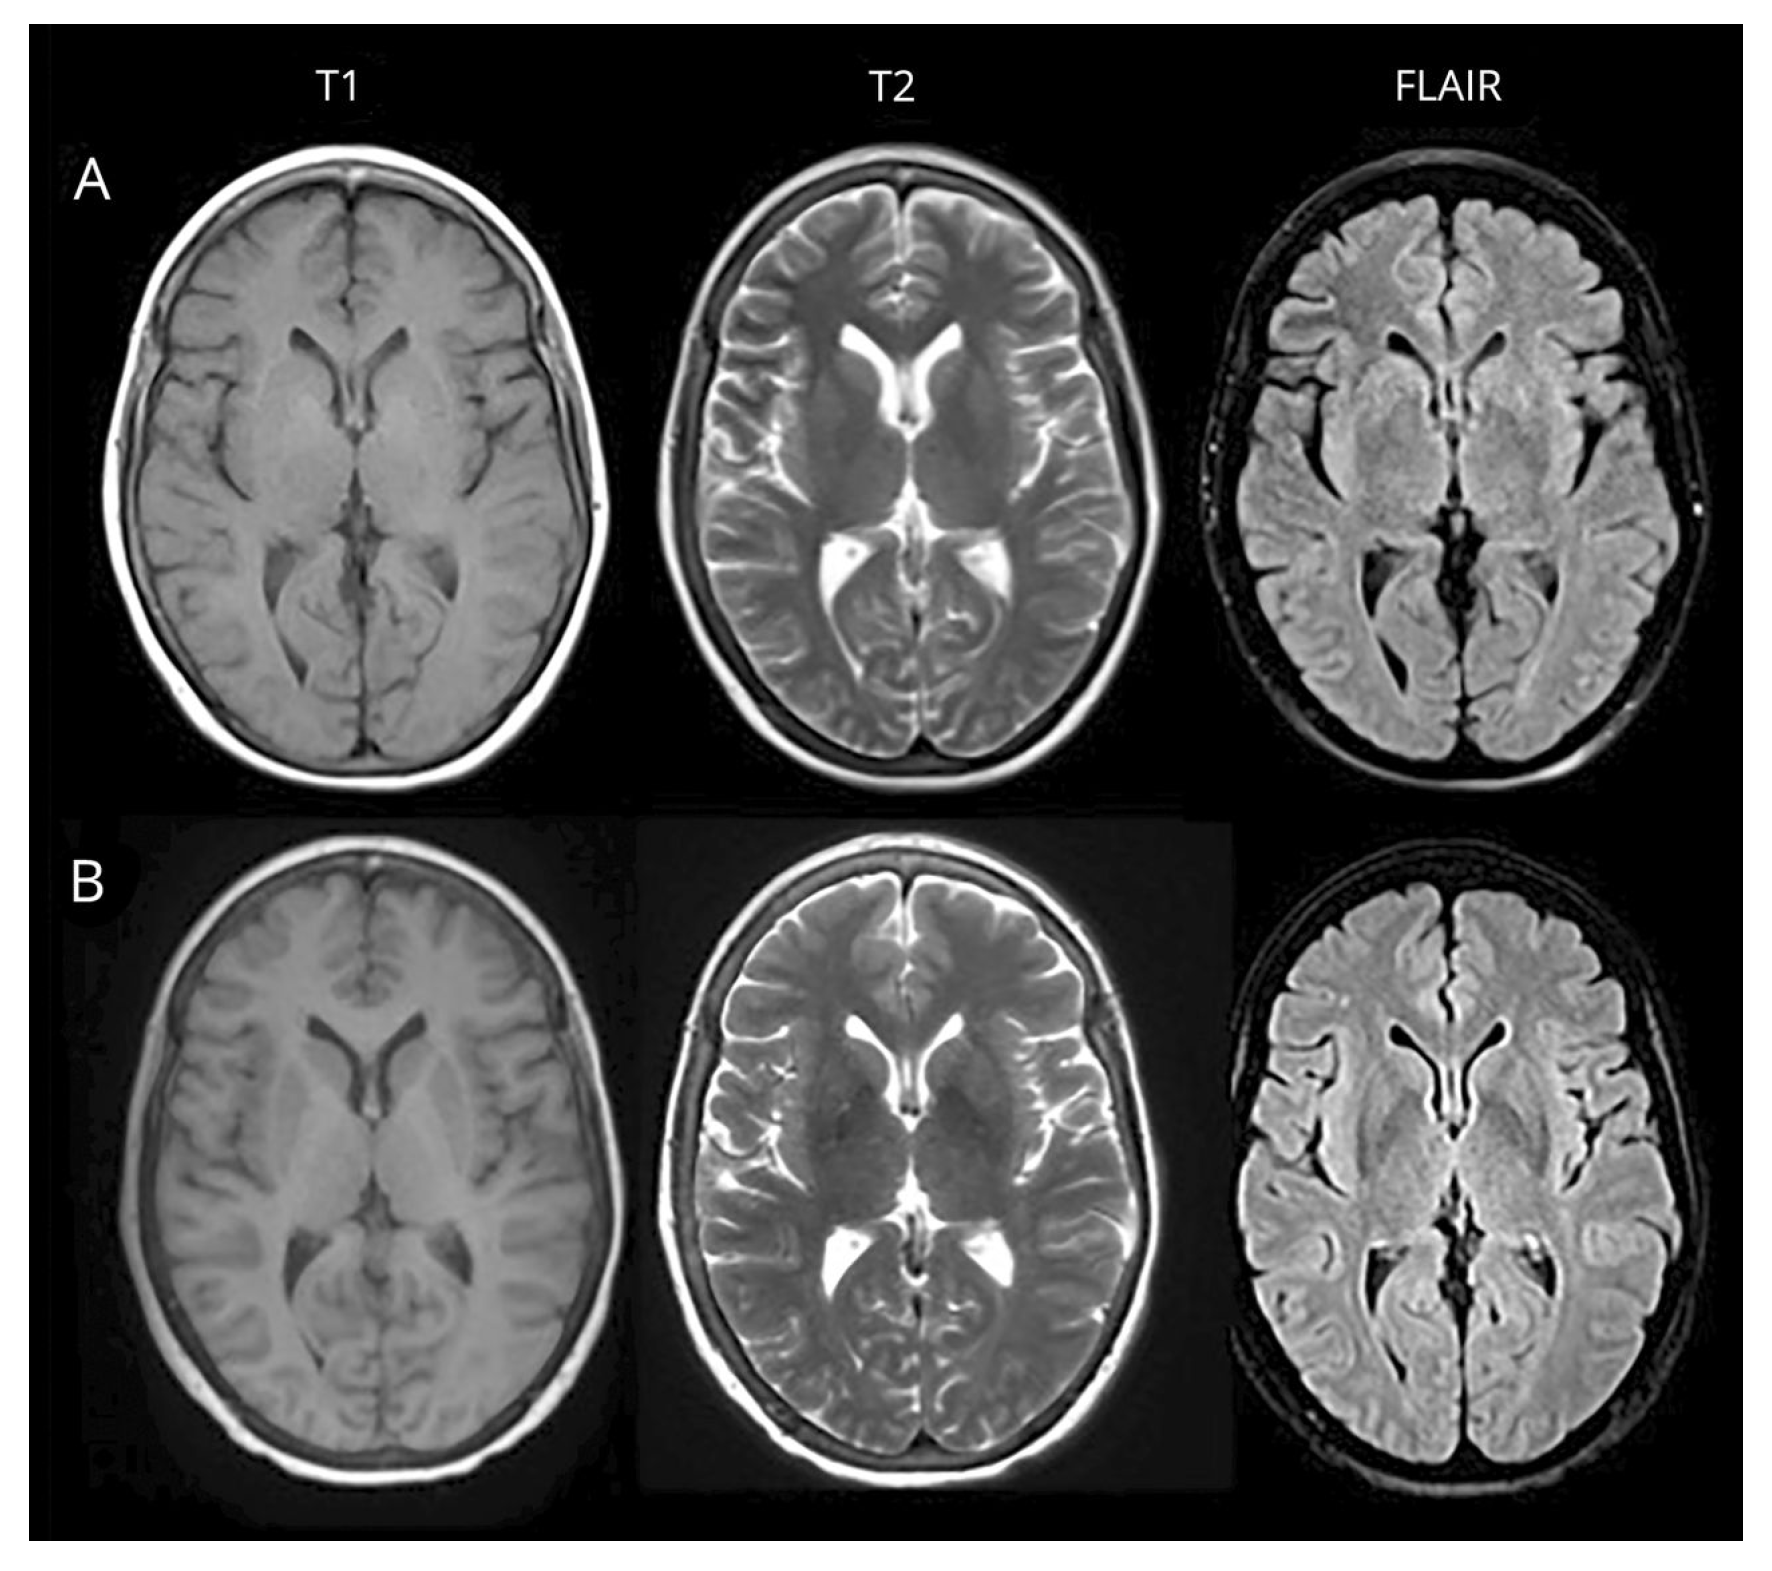

4.3. Dataset

4.4. Image Processing and Classification